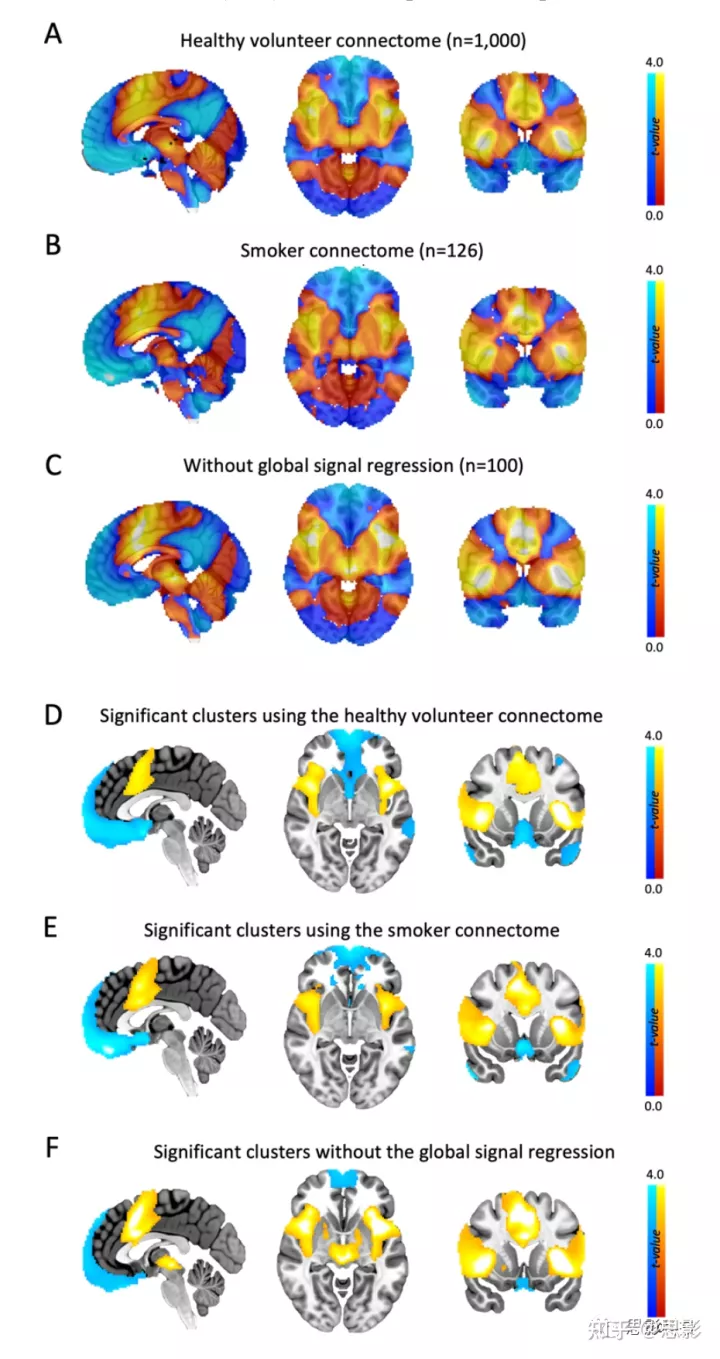

图S7:成瘾缓解网络结果对连接组是稳健的。

与126 名吸烟者(空间相关系数 r=0.94)(B),或在没有全局信号回归的情况下健康志愿者连接组的 rs-fcMRI 数据集相比(r = 0.94,C),我们使用来自 1000 名健康志愿者的 rs-fcMRI 数据集(A)进行初步分析的成瘾缓解网络图保持不变。与无阈值聚类增强(PFWE<0.05)进行多重比较的显著聚类幸存下来的校正也几乎相同 (D-F)。